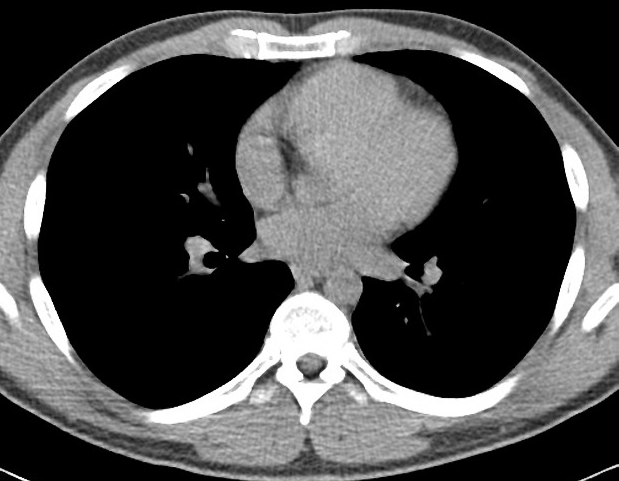

Refer to caption

(a) First-domain dataset (D1D_{1})

(b) Second-domain dataset (D2D_{2})

Figure 2: Examples of chest CT images on the subsets from the J-MID database: (a) First-domain dataset (D1D_{1}) and (b) Second-domain dataset (D2D_{2}).

For pretraining, we utilized a subset of the J-MID111https://www.radiology.jp/j-mid/ database, which contains large-scale CT scans from Japanese medical institutions, and the RICORD dataset [52], an open dataset that was developed collaboratively by the Radiological Society of North America and international partners and contains chest CT scans collected from four countries. Each dataset was constructed with two domains based on mediastinal and lung window settings in chest CT images. Both domains are denoted as D1D_{1} and D2D_{2}, and the labels are not used during pretraining. Specifically, for the J-MID subset, D1D_{1} (the mediastinal window) contains 31,256 CT images, and D2D_{2} (the lung window) contains 26,403 CT images. The RICORD dataset comprises 12,897 D1D_{1} (mediastinal window) images and 11,668 D2D_{2} (lung window) images for pretraining. The corresponding images for each example are shown in Figs. 2 and  3. For fine-tuning and evaluation, we utilized two public datasets: the SARS-CoV-2 CT-Scan Dataset [51] and the Chest CT-Scan Images Dataset222https://www.kaggle.com/datasets/mohamedhanyyy/chest-ctscan-images. Both datasets were used for the coronavirus disease 2019 (COVID-19) and chest-cancer classification tasks, respectively. The data breakdown is as follows: the SARS-CoV-2 CT-Scan dataset comprises 787 training, 197 validation, and 250 test images, labeled into two (COVID-19 and Normal) classes. The Chest CT-Scan Images Dataset comprises 490 training, 123 validation, and 315 test images labeled into four (adenocarcinoma, large-cell carcinoma, squamous-cell carcinoma, and normal) classes.